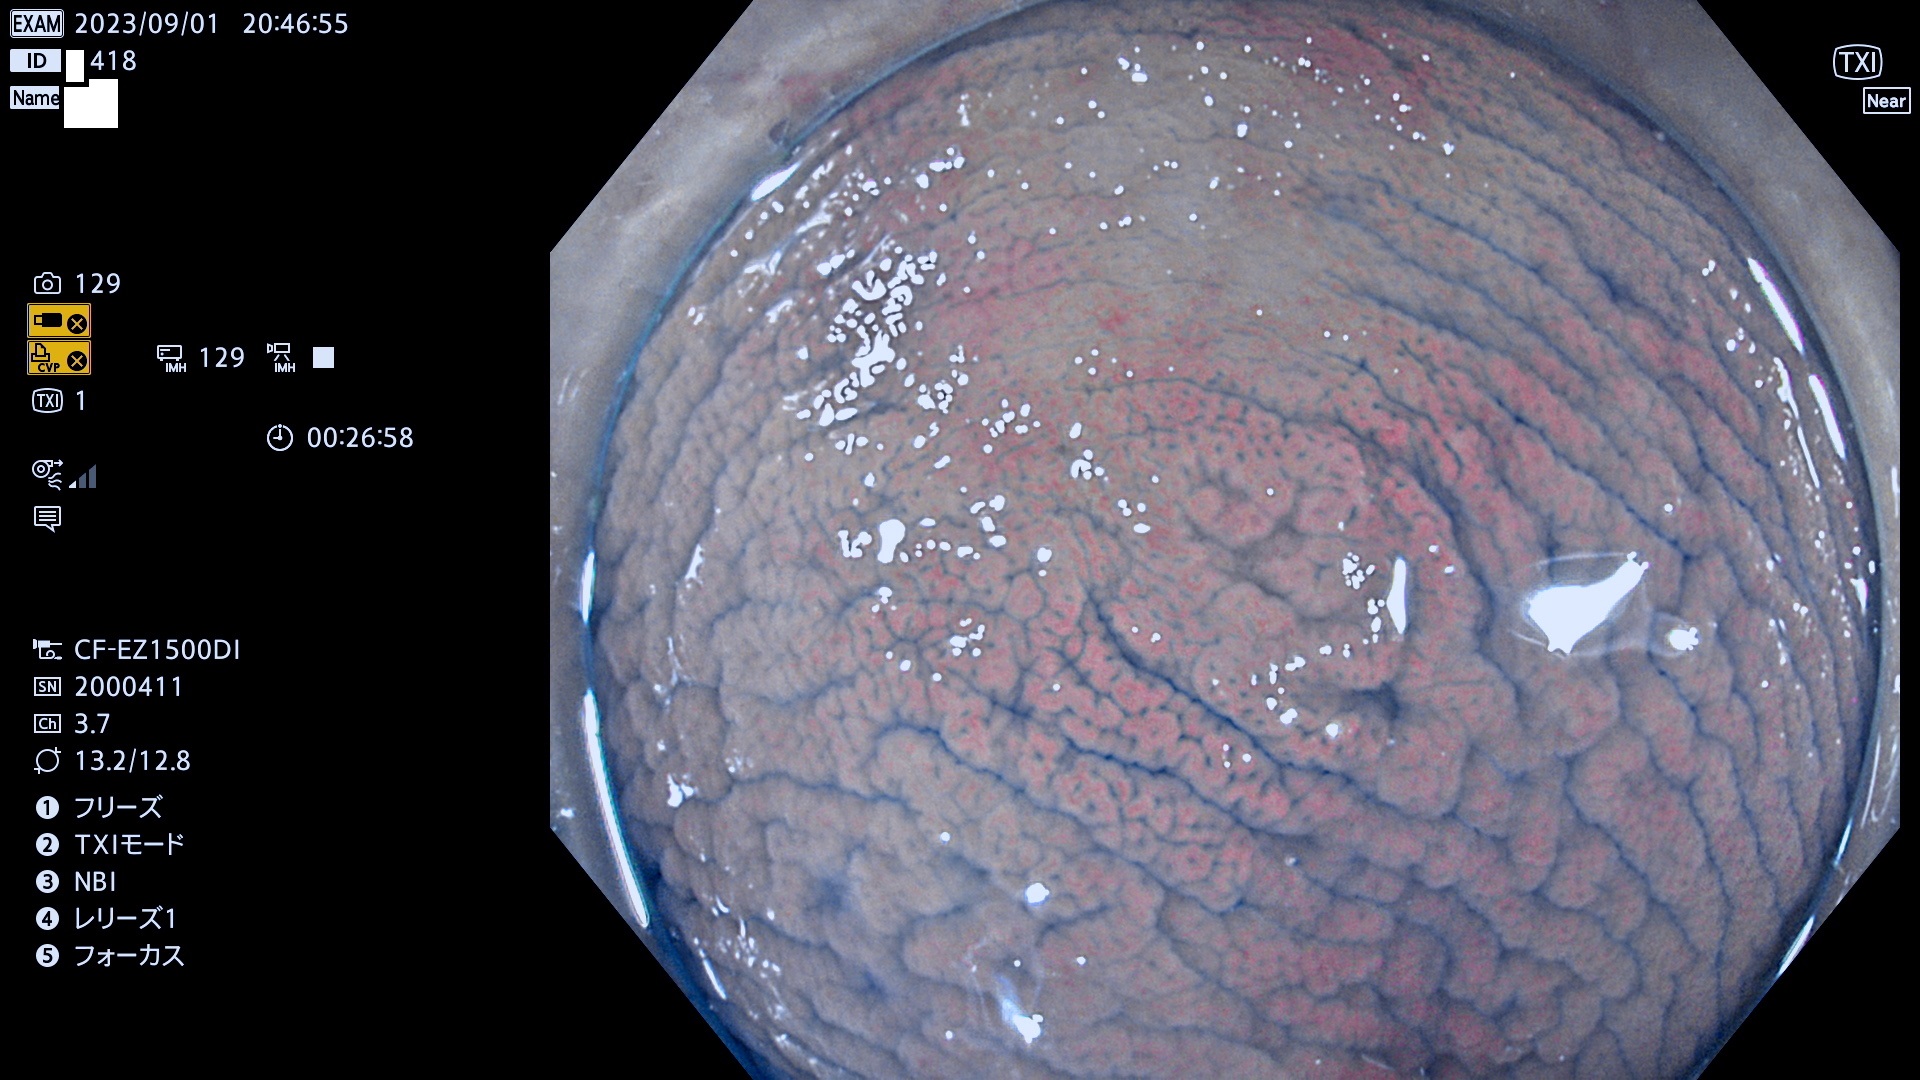

表面型腺腫(Flat Adenoma)の中で、完全に平坦な物をUb、陥凹している物をUcと呼びます。平坦隆起型(Ua)よりも、発見が難しく危険な病変です。このタイプは「内視鏡後・大腸癌の重要犯人」であり、この発見率は「腺腫発見率」よりも、重要な意味があります。

専門的)Uc=De Novo癌? 内視鏡の解像度が低かった時代、このような説もありました。しかし今日の高精度内視鏡では良性の微小なUc型腺腫が日常的に見つかります。私見ですが「Ucこそが多段階発癌(Adenoma-Carcinoma Sequence)のMain Route」と考えます。

毎週の検査(木・金・土・日)に発見されたUb、Uc型・腺腫を、その週の日曜の夜にUPし1週間、提示します。

抽出の対象期間 2023年8月31日(木)〜9月3(日)の4日間(48件の検査)12件